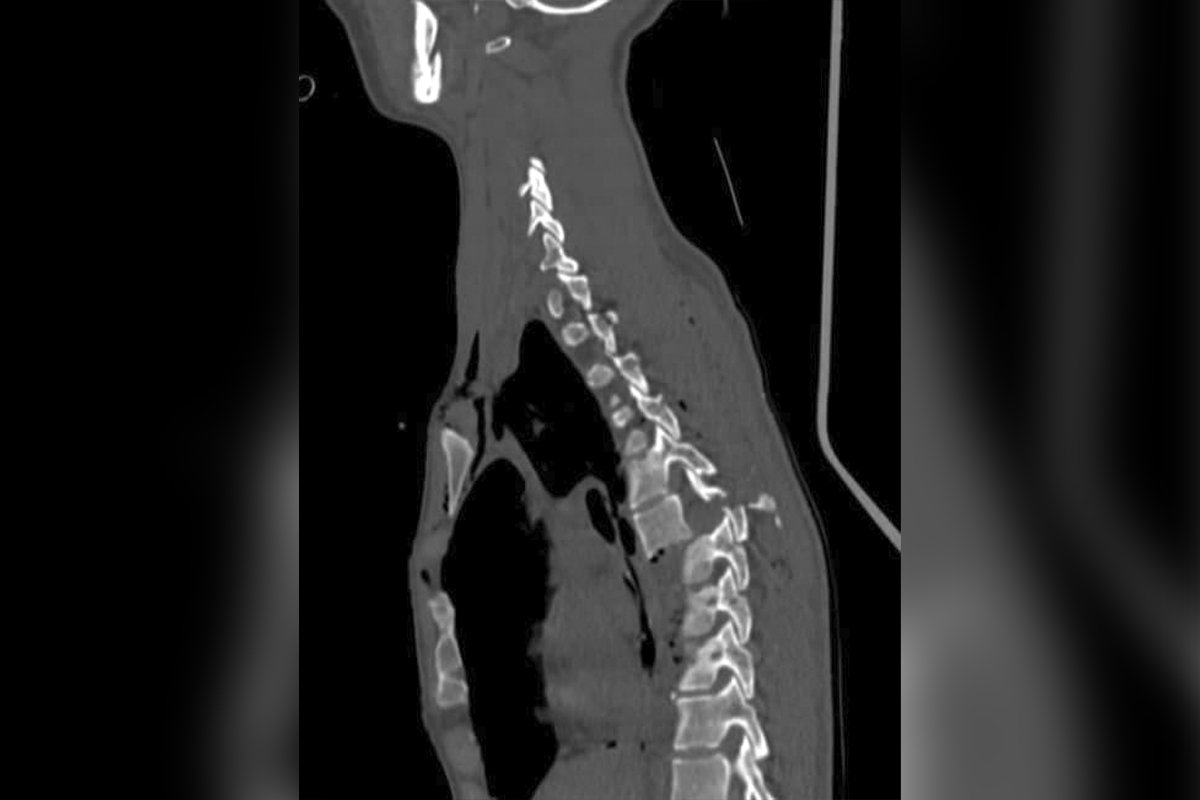

«Она пронеслась над бездной. Каждый час после аварии – подарок судьбы.10 дней реанимации в Мечникова, тяжелейшая черепно-мозговая травма, сотрясение головного мозга. В грудном отделе переломовывих 7 позвонка, разбита грудная клетка. Реаниматолог Екатерина Краснопер, глядя в глаза девушки, чувствует холод по спине - такие не живут. Они ровесники. Доктора понимают, каждое движение может быть последним, неоднократно переливают кровь. Сотни инъекций дают надежду. Состояние стабилизируют. Готовят к операции. Kyrpa Jurij с нейрохирургами из Харькова (институт Ситенко) проводит блестящую операцию, спасая жизнь, а главное, сохраняя функции спинного мозга. Сегодня на утро движения в конечностях активны. Девушка сквозь боль и слезы улыбается. Теперь у нее все впереди», - написал Сергей Рыженко.

По информации знакомого пострадавших, Константина Бычкова, Полину сегодня даже садили. Также он рассказал, что ее сестру, Ирину, которая в результате ДТП получила черепно-мозговую травму, уже выписали из больницы. Мама третьей пострадавшей, Яны Василенко, у которой был перелом шейного отдела позвоночника, информацию о состоянии ее дочери комментировать отказалась, пока продолжается следствие.